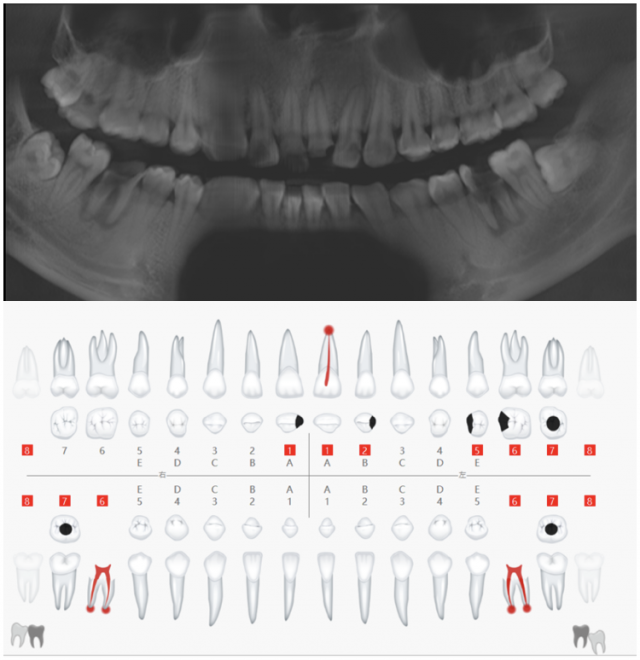

术前影像学资料及口腔检查表

术前口内照片 A.术前唇面照;B.术前黑背板照;C.术前舌侧照;D.术前牙齿宽度测量;E.牙周基础治疗后的比色照;F.偏振光照看牙齿纹理

术前CBCT示根尖周低密度透射影